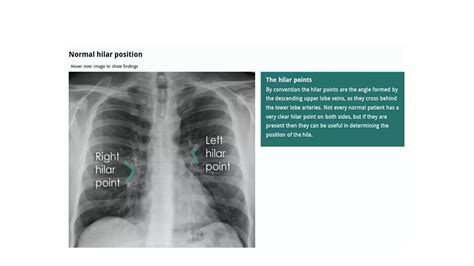

Here are five ways to interpret a normal chest X-ray: * Lung Fields: The lung fields should be clear and free of any abnormalities, such as nodules, masses, or infiltrates. The lungs should also be of equal size and shape. * Heart Size and Shape: The heart should be of normal size and shape, with no signs of enlargement or abnormality. The cardiothoracic ratio, which is the ratio of the heart size to the chest size, should be within normal limits. * Chest Wall and Ribs: The chest wall and ribs should appear normal, with no signs of fractures, deformities, or other injuries. * Diaphragm and Mediastinum: The diaphragm and mediastinum should appear normal, with no signs of abnormalities, such as masses or infiltrates. * Pleura and Airways: The pleura and airways should appear normal, with no signs of abnormalities, such as pleural effusions or airway diseases.

A normal chest X-ray can reveal a lot about a person’s health, including: * Lung Health: A normal chest X-ray can indicate that the lungs are healthy and free of diseases, such as pneumonia or lung cancer. * Heart Health: A normal chest X-ray can indicate that the heart is healthy and of normal size and shape, which can rule out conditions such as heart failure or cardiomegaly. * Chest Wall and Rib Health: A normal chest X-ray can indicate that the chest wall and ribs are healthy and free of injuries or deformities. * Diaphragm and Mediastinum Health: A normal chest X-ray can indicate that the diaphragm and mediastinum are healthy and free of abnormalities.